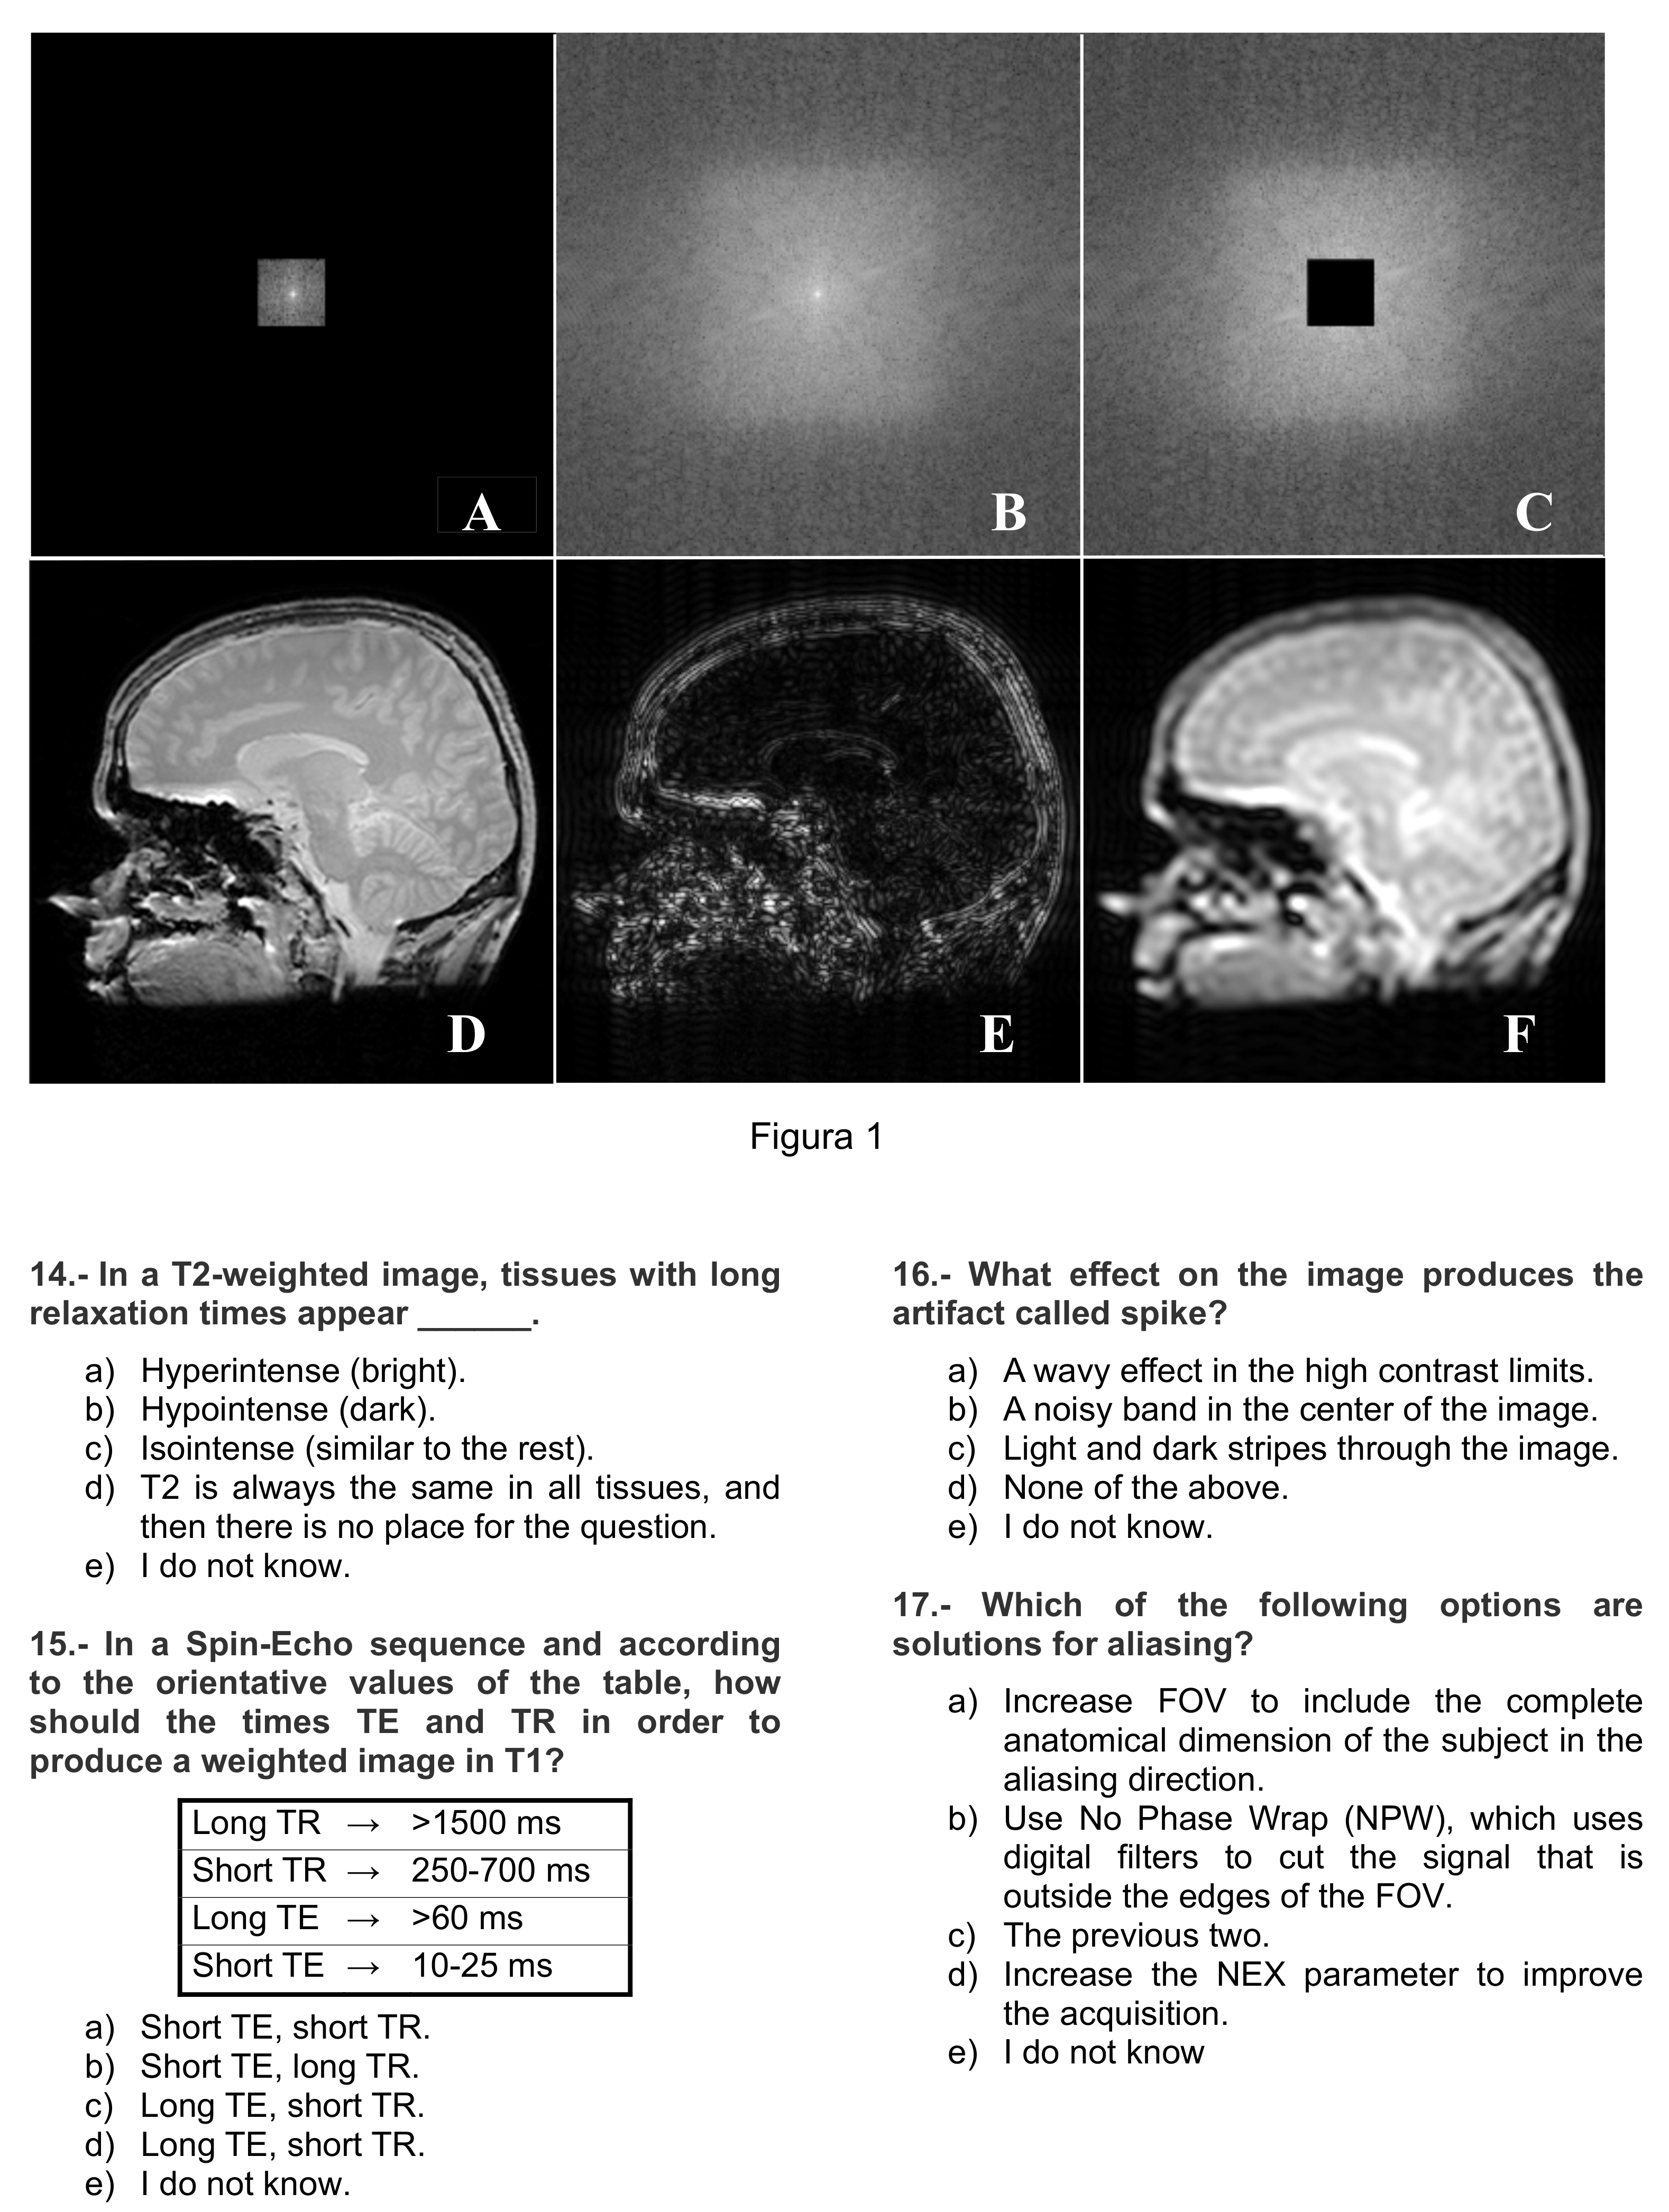

Figure A1.

Instrument page 1 of 4.

Appendix B shows the questionnaire translated into English. Each item has four possible answers together with the answer “I do not know”; the latter intends to avoid random answers. The first 10 items correspond to the content of the first lecture, as enumerated in Section 2.3, while the remaining items correspond to the content of the second lecture. Since the content of this first part deals with theoretical aspects of MRI and was presented in a purely explanatory way, we will hereafter refer to it as “theoretical” part or “T part”, while the second will be hereafter referred to as “practical part” or “P part”. The score of the questionnaire is the number of correct answers (hereafter referred to as “hits rating”); hence the maximum score is 10 points in each part. This score will be used by default. For the sake of completeness, a null-expectation version of the rating—random answering leads to an average zero score—has also been accounted for.